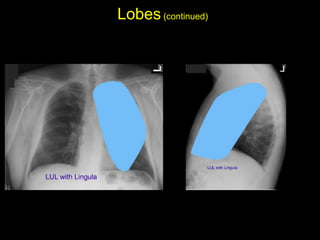

The document discusses the anatomy of the chest x-ray and CT scan by describing the lobes of the lungs and their locations. It also mentions the heart, mediastinum, hilum, and ribs. Several axial, coronal, and sagittal CT images are included with labels pointing out structures like the trachea, bronchi, lobes of the lungs, and fissures. In summary, the document provides an overview of lung and chest anatomy as seen on x-rays and CT scans through text descriptions and labeled medical images.